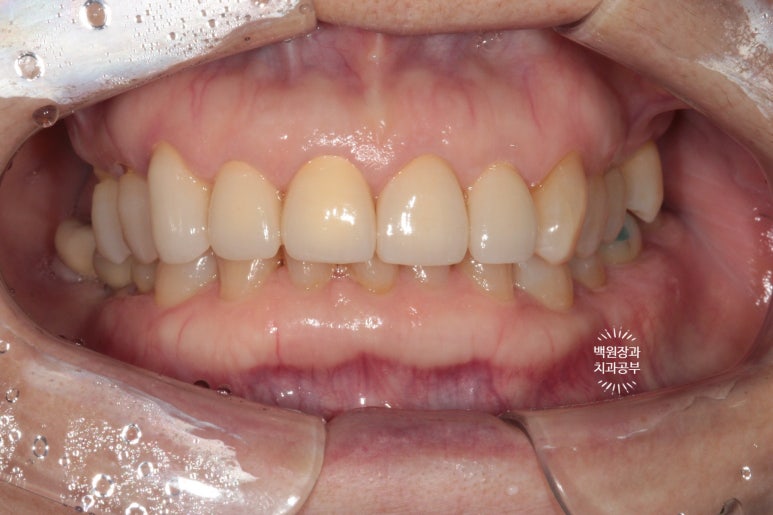

확실히 가지런해진 모습인데요, 인위적으로 색상이 밝은 것 같다고 다른 치아와 유사한 색상으로 만들어 싶어하셨어요.

음.. 대부분의 환자들이 보통 앞니 크라운 치료시 보다 밝은 색상을 원하시는데, 치과의사가 좋아하는 정확한 내 치아색을 원해하셔서 조금의 수정을 해보기로 하였습니다.

짜잔~ 조금의 차이점이 느껴지시나요?

치아의 목부분 (치경부)의 색상이 약간 yellowish하게 수정되었습니다.

보다 더 자연스러운 느낌이에요!